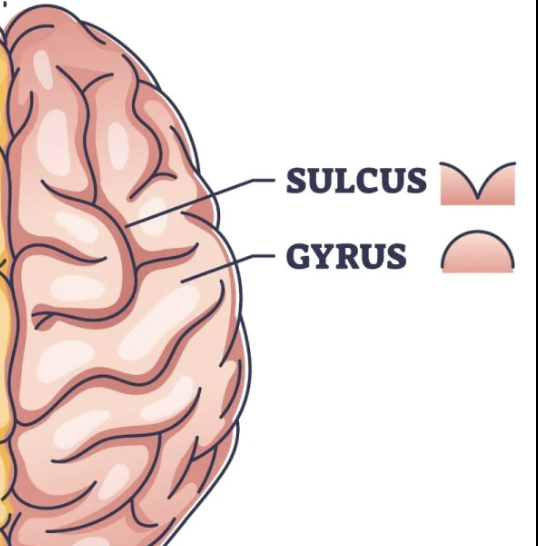

What are the ridges (folds) on the cerebrum called?

Gyrus/Gyri (Peak of the sunchip)

What are the grooves(valley) on the cerebrum called?

Sulcus/Sulci valley between the peak